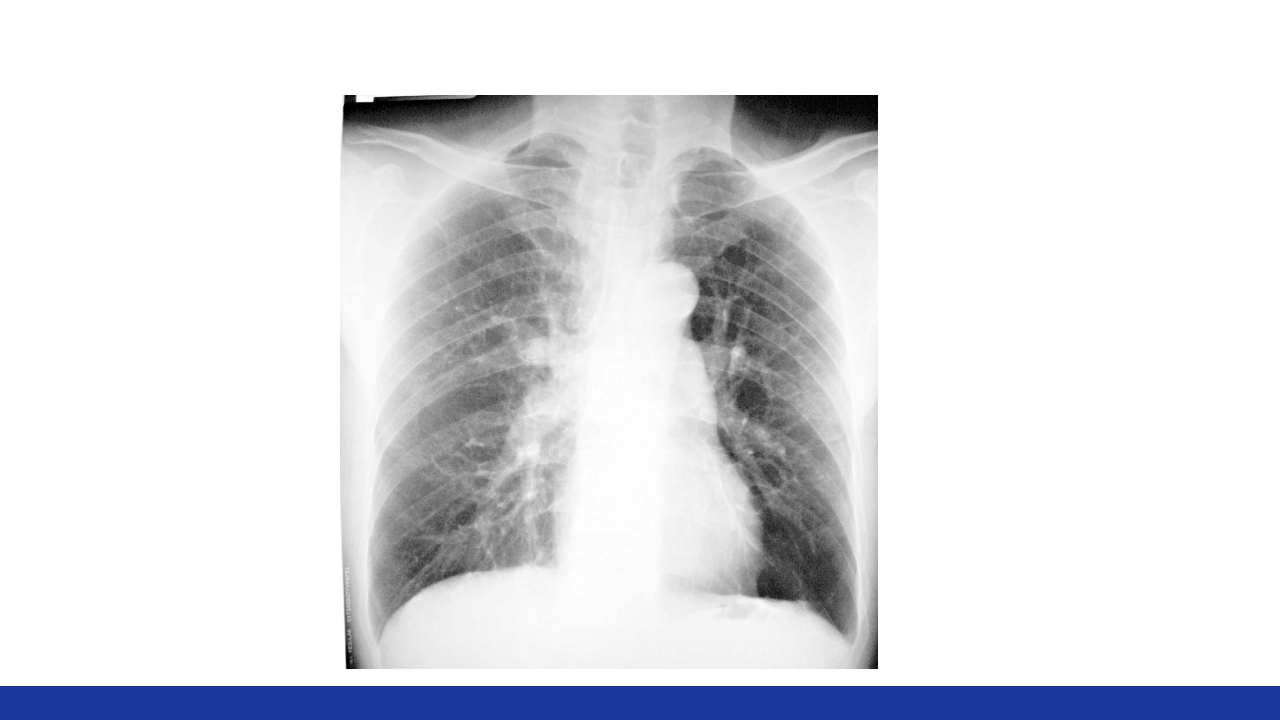

慢性肺源性心脏病 Chronic Pulmonary Heart Disease 主讲人:XXX 教学目标 【掌握】 1.慢性肺源性心脏病病人的护理护理评估。 2.慢性肺源性心脏病病人的临床表现与并发症。 3.慢性肺源性心脏病病人的护理措施。 【熟悉】 慢性肺源性心脏病的主要护理诊断及治疗要点; 【了解】 慢性肺源性心脏病的病因及发病机理。 案例 男性,63岁。慢性咳嗽、咳痰20余年,逐渐加重的呼吸困难5年。有吸 烟史40年左右。T 36.2℃,BP 130/80mmHg,神志清,胸廓呈桶状,双 肺叩诊过清音,触觉语颤减弱,肺泡呼吸音减弱,肺动脉瓣区第2心音 亢进,三尖瓣区可闻及收缩期杂音。血白细胞10×109/L,中性粒细胞 70%。X线胸片:双肺透亮度增高,肺动脉扩张。 问题:①临床诊断? ②主要护理问题? ③健康指导? 定义...